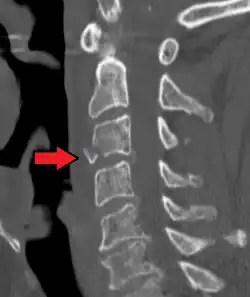

![]() | |

| A fracture of the base of the dens (a part of C2) as seen on CT | |